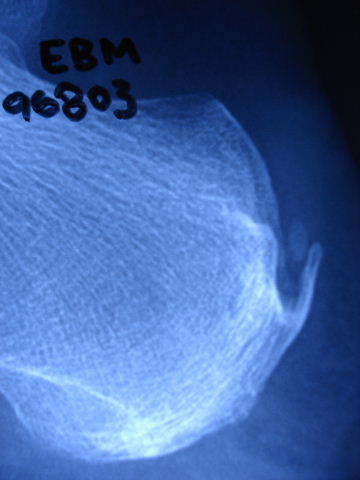

E de Paget